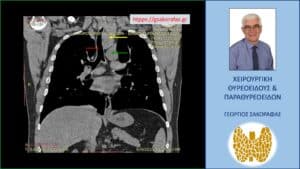

Καταδυόμενη βρογχοκήλη με κατάδυση σε βάθος στο θώρακα – εικόνα στην αξονική τομογραφία (κατά μέτωπο διατομή, σε άλλο επίπεδο). Εμφανής η μεγάλου βαθμού διόγκωση και η κατάδυση σε βάθος του αριστερού λοβού (κίτρινο βέλος), που φθάνει στις παρυφές του αορτικού τόξου (πράσινο βέλος), με την τραχεία (κόκκινο βέλος) να απωθείται προς τα δεξιά από τον διογκωμένο αριστερό λοβό. Ο καταδυόμενος αριστερός λοβός φθάνει σε βάθος λίγο πιο πάνω από τον διχασμό της τραχείας στους δύο στελεχιαίους βρόγχους.